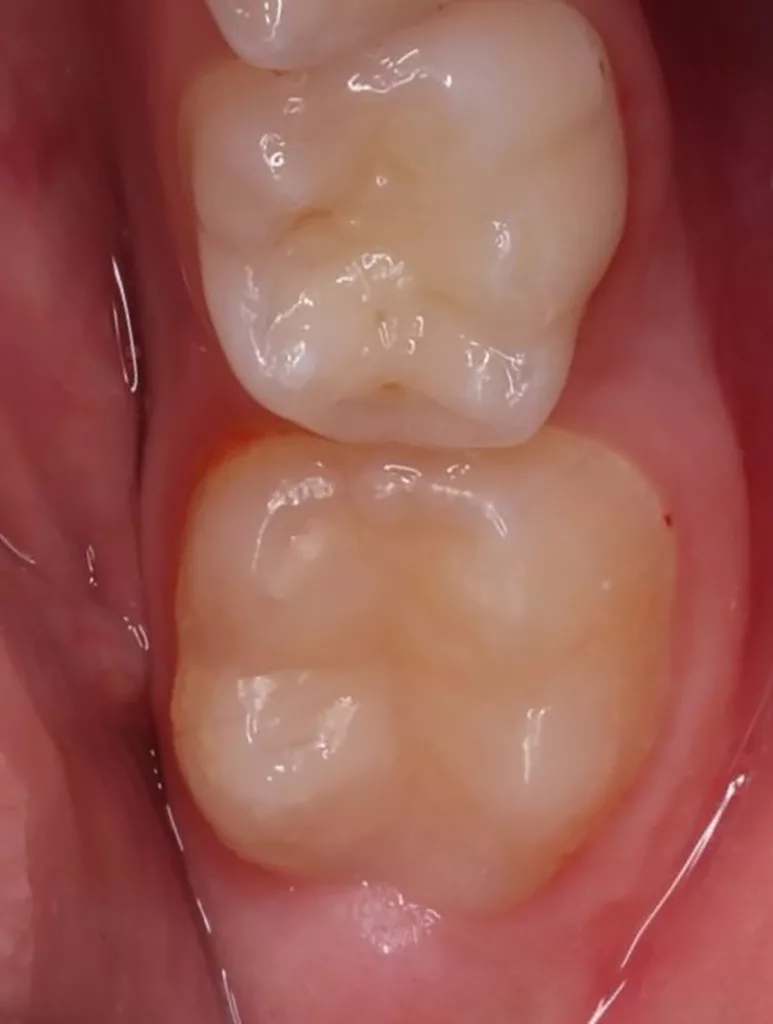

Im Rahmen der jährlichen Kontrolluntersuchung wurde bei einem achtjährigen Mädchen auf der routinemäßig angefertigten Röntgenaufnahme eine mittelgroße PEIR des Zahnes 46 (Grad 2 der Läsion nach Seow) entdeckt (Abb. 43). Die Patientin war komplett beschwerdefrei und der Zahnschmelz des betroffenen Zahnes sah intakt aus (Abb. 44 und 45). Weil auch hier der PEIR-Defekt gräulich durchschimmerte (Abb. 44 und 45) und der Zahn bereits seit einem Jahr durchgebrochen war, entschieden wir uns in diesem Fall, den Defekt klassisch mit Komposit zu restaurieren. Unter Lokalanästhesie mit Septanest 1/100 000 (Septodont, Frankreich) wurde zunächst Kofferdam mithilfe der Klammer U67 (KSK Dentech, Japan) gelegt (Abb. 45). Weder visuell noch mittels Sondierung konnte eine Verbindung zur Läsion festgestellt werden. Deswegen wurde an der Stelle, an welcher der PEIR-Defekt gräulich schimmerte, intakter Zahnschmelz der lingualen Querfissur entfernt (Abb. 46). Innerhalb der Läsion wurde nekrotisches intrakoronales Weichgewebe vorgefunden (Abb. 47), das problemlos mittels RONDOflex plus 360 (KaVo Dental, Deutschland) mit dem 27-µm-Pulver vollständig entfernt werden konnte. Der Boden des Defektes zeigte eine glatte, runde Form sowie helles, hartes und intaktes Dentin. Eine Präparation war nicht erforderlich, es wurde lediglich die Zahnschmelzkante geglättet (Abb. 48). Für die Restauration kamen erneut das Adhäsiv Optibond FL (Kerr, USA) und das Komposit Estelite ASTERIA OCE, A2B und Universal Flow AO2 (Tokuyama, Japan) zur Anwendung (Abb. 49). 6 Monate nach der Behandlung zeigte sich das Ergebnis sowohl aus klinischer als auch radiologischer Sicht stabil wie die Abbildungen 50 und 51 zeigen.